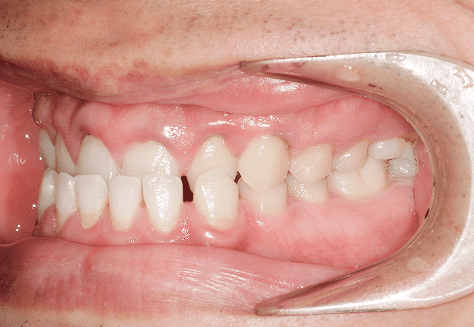

M.U

治療前

治療後

主訴

下の歯が特にガタガタなのが気になる。上の前歯が1本反対になっている。

診断

下顎前突・叢生・反対咬合

年齢/性別

20代/男性

抜歯部位

非抜歯

使用装置

上下インビザライン(PBM使用)

保定装置

ビベラリテーナー

料金

初回資料採得・・・・・・・30,000円

診断料・・・・・・・・・・33,000円

動的治療終了時資料採得・・5,500円 -

基本料金

950,000円

診察料金

5,500円×16回

治療期間

1年7カ月